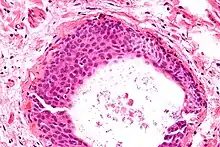

Histologically, there are nests of transitional epithelial (urothelial) cells with longitudinal nuclear grooves (coffee bean nuclei) lying in abundant fibrous stroma.

The coffee bean nuclei are the nuclear grooves exceptionally pathognomonic to the sex cord stromal tumour, the ovarian granulosa cell tumour, with the fluid-filled spaces Call–Exner bodies between the granulosa cells.[4][5]

Micrograph of a Walthard cell nest, the entity Brenner tumours are thought to arise from. H&E stain.